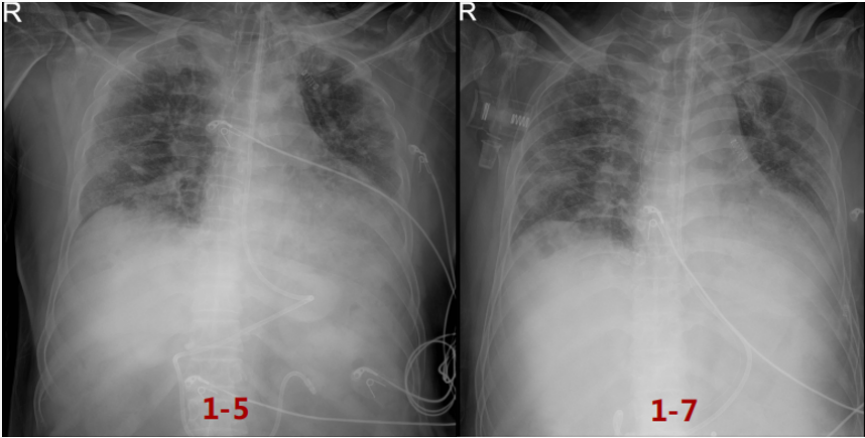

患者,男性,73岁,主诉:发热10天,呼吸困难5天。入院时间:2022年12月25日。10天前患者因接触新冠感染家属后出现发热,伴咳嗽,无痰,体温最高38.4℃,自服布洛芬后体温可下降,但仍反复,体温波动于37.8~38.3℃。5天前于静息状态下感呼吸困难,咳嗽、咳黄痰,未用药,症状持续不缓解。3天前至当地医院就诊,完善胸部CT示“肺部感染”。2天前,测指脉氧饱和度70%左右,收入望京医院ICU病房,住院期间予“莫西沙星、糖皮质激素”治疗后症状无缓解,经120转入我院继续治疗。外院胸部CT可见右肺上叶有一较大空腔,右肺上叶胸膜下有一不规则结节,双肺弥漫磨玻璃影,下肺和胸膜下为著。既往史、个人史及家族史

胸部CT可见右肺上叶肺大泡、不规则结节,双肺弥漫磨玻璃影。初始治疗方案

巴瑞替尼4 mg qd×2 d(12-26,12-28)抗炎。患者于普通病房时氧合进一步恶化,在HFNC FiO2 1.0条件下,氧饱和度波动于80%~85%,患者于2023年12月28日转入MICU。患者状态:神清,呼吸窘迫,RR 33次/min,PFR 86.2 mmHg,立即予以气管插管及呼吸机辅助呼吸。呼吸机参数:PC模式,PC 18 cmH2O,PEEP 10 cmH2O,FiO2 0.9。Crs 30 L/cmH2O,R 12.3 cmH2O·S/L,Vt 300 ml,MVe 10.7 L。血气分析(FiO2 0.9):pH 7.03,PaCO2 128 mmHg,PaO2 128 mmHg,BE -4.2 mmol/L, HCO3- 24 mmol/L,cLac 0.8 mmol/L,PFR 146 mmHg。

患者前期明确有曲霉感染,遂停用了抗炎治疗。经过前期治疗,患者氧合有所改善,但影像学表现欠佳,此时能否脱离ECMO单用有创机械通气支持?下一步抗炎,还是加强抗感染?炎症方面:患者前期经过抗炎治疗,CRP水平降至4.68 mg/L,IL-6水平进行性升高(1539→1898.25 pg/ml,与IL-6受体拮抗剂作用机制有关),Fet明显升高(756.7→1389.1 ng/ml)。免疫方面:患者当前LYM 0.29×109/L,一方面可能提示其免疫功能欠佳,另一方面,炎症反应非常活跃时会诱导淋巴细胞加速凋亡,淋巴细胞进入组织可导致外周血淋巴细胞计数下降。感染方面:经过抗感染治疗,患者体温正常,镜下痰量不多,WBC、PCT正常;多次监测病原学,最近一次BALF GM转阴。1月6日加用托珠单抗480 mg抗炎治疗。1月7日复查胸片可见双肺渗出有所吸收,将ECMO血流量降至2.8 L/min。呼吸机FiO2 0.3,氧合似乎能够维持在稳定状态。截至本专题讲课时,患者仍在进一步治疗。